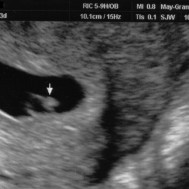

Baby: Week 6

You’re now making spontaneous movements, and can twitch your trunk and limb buds

Each day, changes make you more recognisable as a small person just like you. Now your lungs are forming![1] Brain function, as measured by EEG waves, can be recorded within days.[2] Nerve cells in the brain are connecting, forming primitive neural pathways. Your hands can bend at the wrist, and webbing is disappearing from your feet. Your tail is just about gone. Tastebuds are forming on your tongue.[3] You’re now making spontaneous movements, and can twitch your trunk and limb buds.[4]